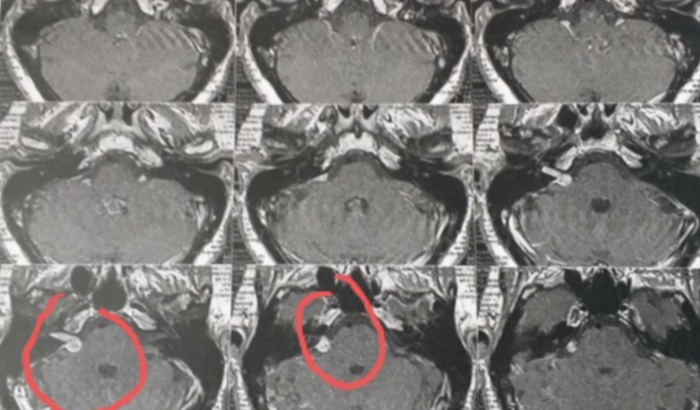

Eu sou Ivonete Camilla, e descobri um neurinoma e, venho pedir se possivel a colaboração para que possa completar e realizar a cirurgia que é na base do crânio, uma cirurgia delicada e cara 85 mil, e neurinoma esta no grau 3, mesmo pq o tratamento é somente cirurgia. A economia que tenho nao consigo por isso meu pedido de ajuda p/completar , estou correndo e tentando tdas alternativas para conseguir e, toda ajuda será bem aceita. Agradeco🙏 Estou correndo e confiante tudo dara certo no momento exato.